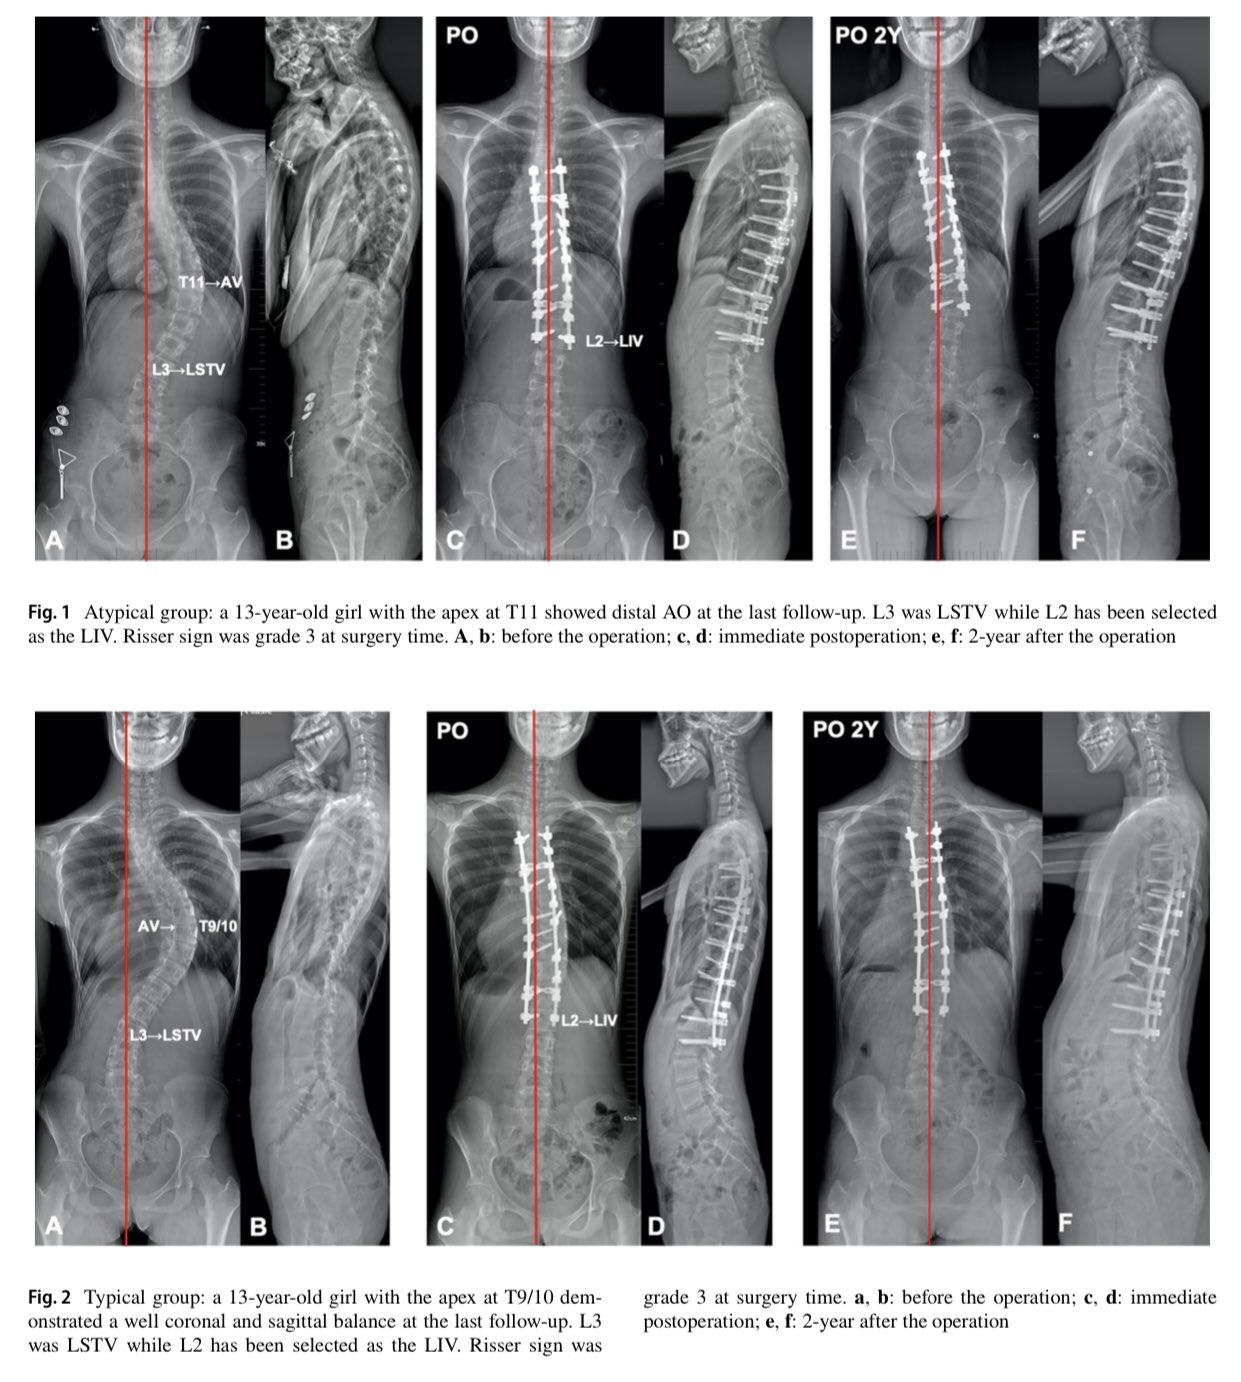

Identificar las características y la incidencia de adición (AO) en pacientes con escoliosis idiopática adolescente Lenke 1A atípica e investigar si la curva Lenke 1A atípica y típica debe seguir la misma estrategia de selección de vértebra instrumentada más baja (LIV).

La curva atípica de Lenke 1A tenía sus propias características radiográficas. Era más probable que se desarrollara AO cuando LIV estaba próximo a la última vértebra sustancialmente en contacto (LSTV), lo que indicó que se deben considerar diferentes niveles de fusión en estos dos subtipos de Lenke 1A. Recomendamos la última vértebra sustancialmente en contacto (LSTV) como LIV en casos atípicos de Lenke 1A, mientras que un nivel proximal a la última vértebra sustancialmente en contacto (LSTV) podría estar disponible en la curva típica de Lenke 1A.

Yin R, Qin X, He Z, Liu Z, Qiu Y, Zhu Z. Which thoracic curves are at the greater risk for distal adding-on: comparison between typical and atypical Lenke 1A curves. Eur Spine J. 2021 Mar 29. doi: 10.1007/s00586-021-06721-7. Epub ahead of print. PMID: 33782755.